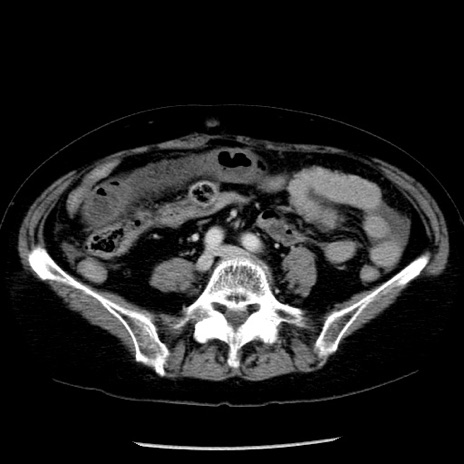

症例13(横断像)

【症例】70歳代女性

【主訴】腹痛、嘔吐

【現病歴】15時間程前(昨晩)より腹痛あり。今朝になっても症状の改善なく、嘔吐あり。腹痛も増悪あり、救急外来受診。

【既往歴】子宮癌全摘術後

【身体所見】意識清明、BP 121/72mmHg、P 74bpm、SpO2 100%(RA)、腹部:平坦・軟、腸雑音ほぼ聴取せず。下腹部・心窩部・臍左上に圧痛あり。反跳痛なし。

【データ】WBC 10600、CRP 0.15